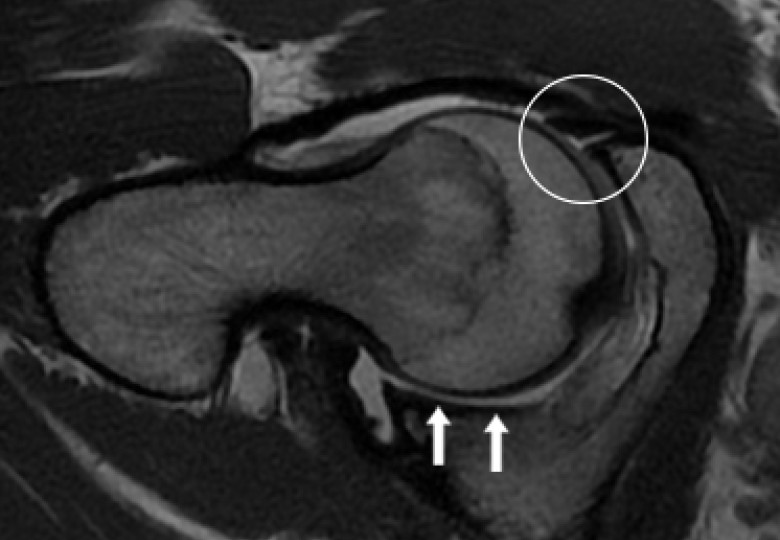

- Labral hyperplasia ( enlargement of the cartilage at the margin of the hip socket) was a predictor of microinstability.